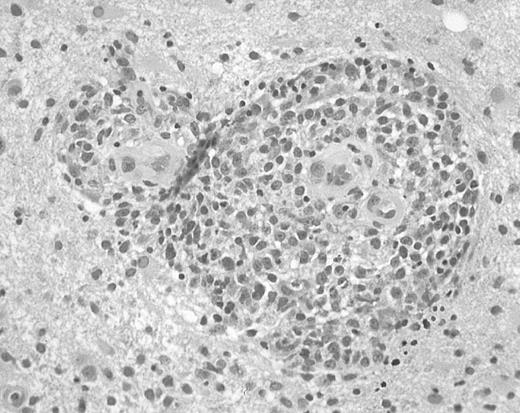

Brain biopsy specimens from 24 patients with non-Hodgkin B-cell PCNSL were studied. Specimens varied in size, most consisting of multiple pieces that varied from fragments measuring less than 0.1 × 0.1 cm to pieces measuring 2.0 × 0.9 cm. Microscopic examination revealed diffuse invasion of brain parenchyma by medium-sized or large atypical lymphocytes. The characteristic pattern of preferential concentric perivascular cuffing by malignant lymphocytes was observed in most cases, particularly in less densely infiltrated tissue or at the tumor periphery (Figure1). According to WHO criteria, 23 tumors were classified as diffuse large B-cell lymphomas and one tumor was classified as an atypical Burkitt lymphoma.

Histopathology of PCNSL.

Brain biopsy specimen from a patient with PCNSL shows infiltration of brain tissue by large malignant lymphocytes, with characteristic perivascular collections of tumor cells (hematoxylin and eosin, original magnification × 400).